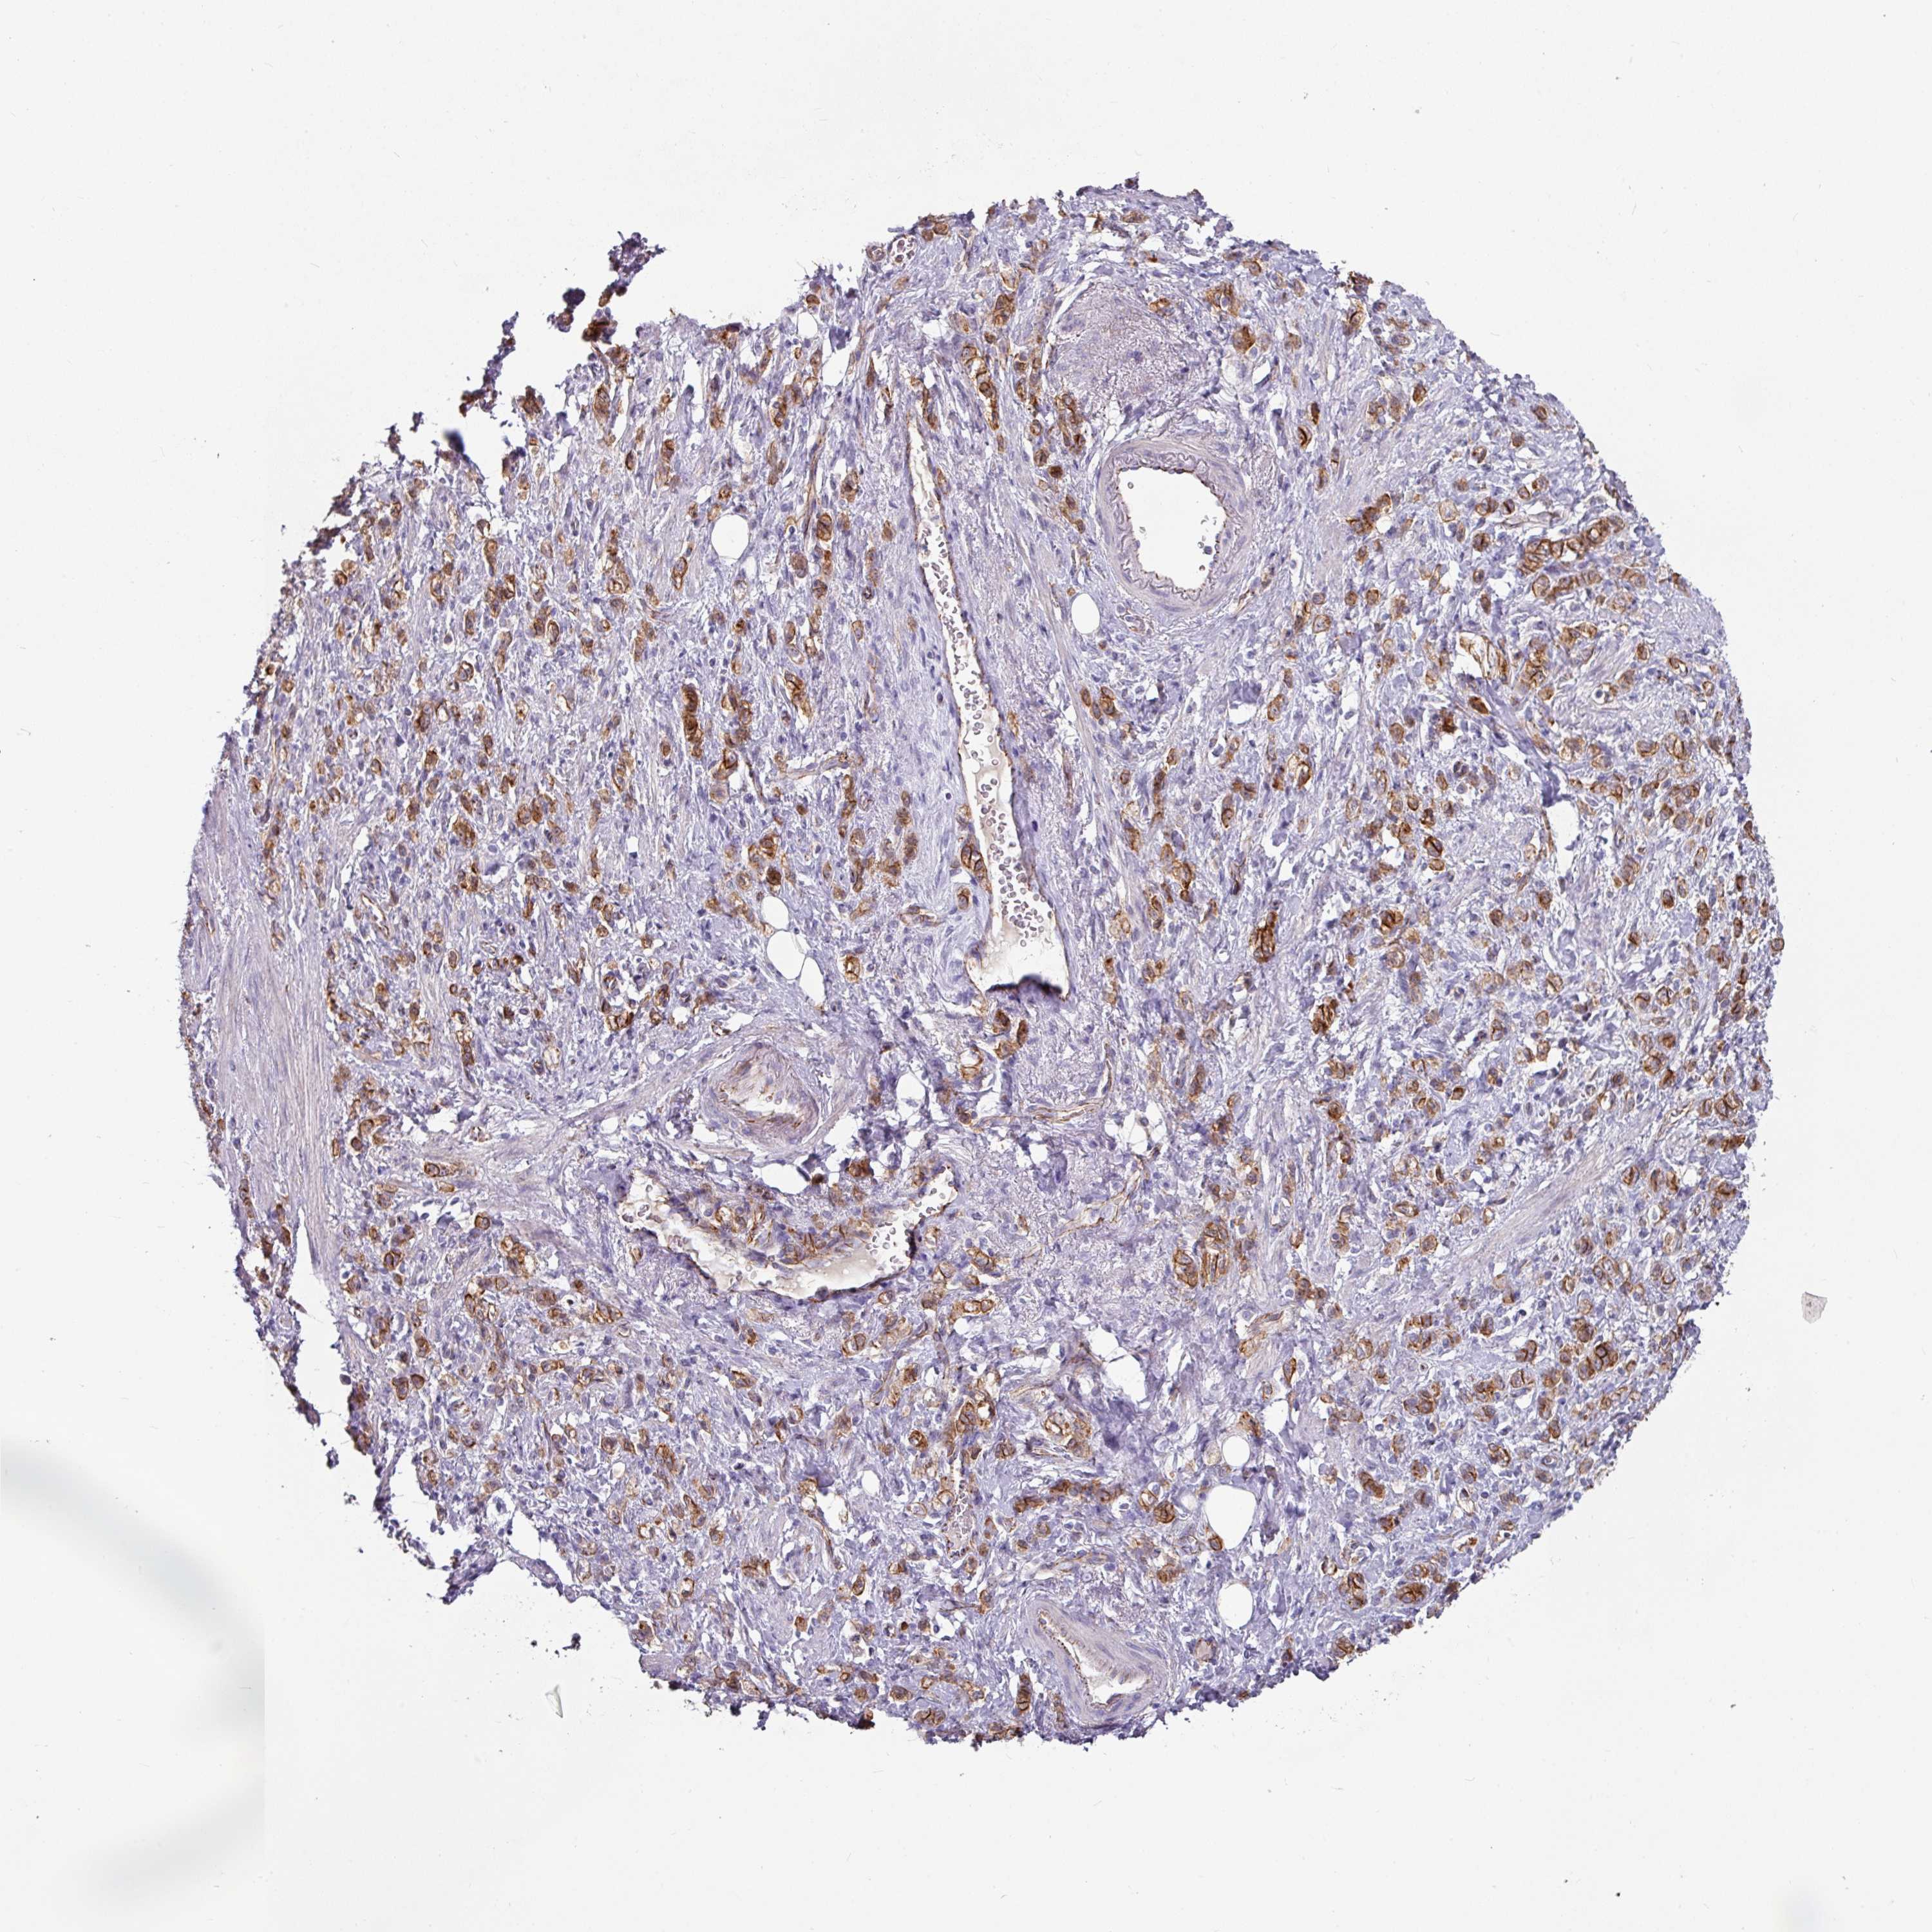

STOMACH CANCER - Protein expressioni

A mouse-over function shows sample information and annotation data. Click on an image to view it in a full screen mode. Samples can be filtered based on level of antibody staining by selecting one or several of the following categories: high, medium, low and not detected. The assay and annotation is described here.

Note that samples used for immunohistochemistry by the Human Protein Atlas do not correspond to samples in the TCGA dataset.

Antibody stainingi

Antibody staining in the annotated cell types in the current human tissue is reported as not detected, low, medium, or high, based on conventional immunohistochemistry profiling in selected tissues. This score is based on the combination of the staining intensity and fraction of stained cells.

Each image is clickable and will lead to virtual microscopy that enables deeper exploration of all samples and also displays staining intensity scores, fraction scores and subcellular localization as well as patient and tissue information for each sample.

Antibody HPA032047

Antibody CAB002139

Staining

High

Medium

Low

Not detected

Intensity

Strong

Moderate

Weak

Negative

Quantity

>75%

75%-25%

<25%

None

Location

Nuclear

Cytoplasmic/membranous

Cytoplasmic/membranous,nuclear

Adenocarcinoma, NOS